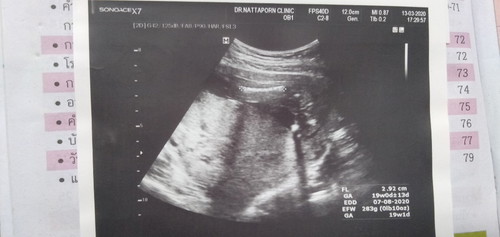

เพศลูก

อยากให้แม่ๆช่วยดูว่าตรงนี้ใช่เพศลูกไหมคะ ถ้าใช่ ผู้หญิงหรือผู้ชายค่ะ คุณหมอไม่ได้บอกแม่เลยค่ะ

มองไม่ค่อยชัดเลยค่ะ ซูมแล้วซูมอีก น่าจะหญิงนะคะ ไม่เห็นป๋องแป๋งกับไข่